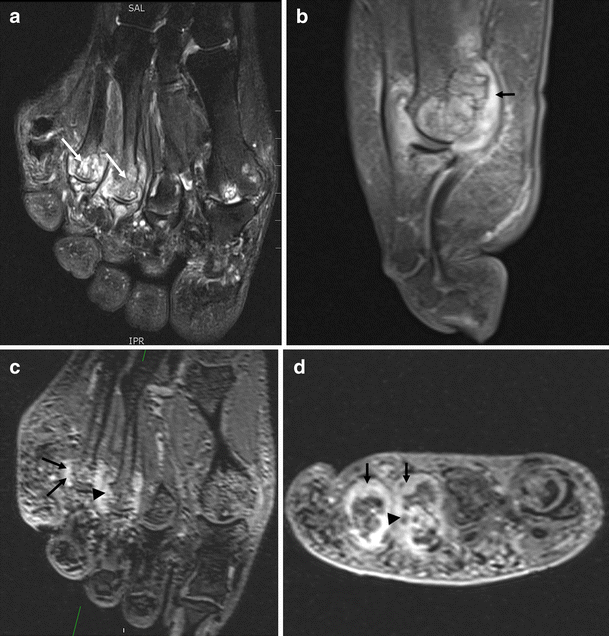

From casereports.bmj.com

Multiple tendon xanthomas in patient with heterozygous familial Plantar Xanthoma Mri Ultrasound and mri should be. This review article exemplifies simple and systematic guidelines for imaging assessment of plantar fascia disorders, with a focus on key findings detectable on plain radiography, ultrasound and magnetic resonance imaging (mri). Some of the more common causes include achilles tendinosis, haglund phenomenon, and plantar fasciitis. Thickening and signal changes in the pf as well as. Plantar Xanthoma Mri.